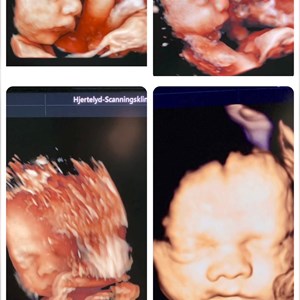

Hjertelyd - scanningsklinik for gravide

Sødeste lille nus 😍 Denne pige var på besøg i dag - hendes mor og far samt mormor og far...